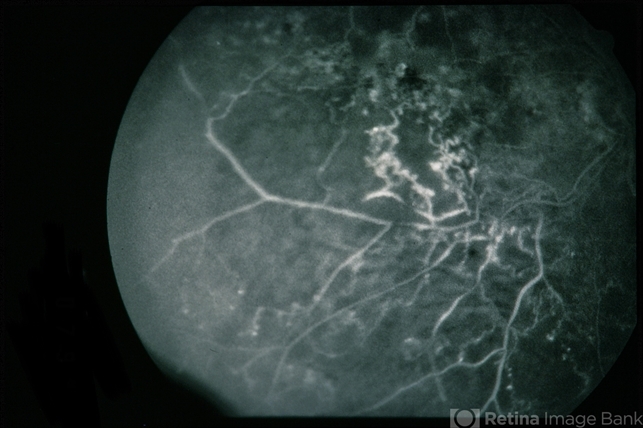

- BRVO Massive Exudate from Collaterals

- Condition/keywords

- branch retinal vein occlusion (BRVO), exudate, collaterals

- 66-year-old female with BRVO - massive exudate from collaterals, 20/70 OD; 20/25 OS in 1985; +HTN, glaucoma; 20/200 OD 1987.